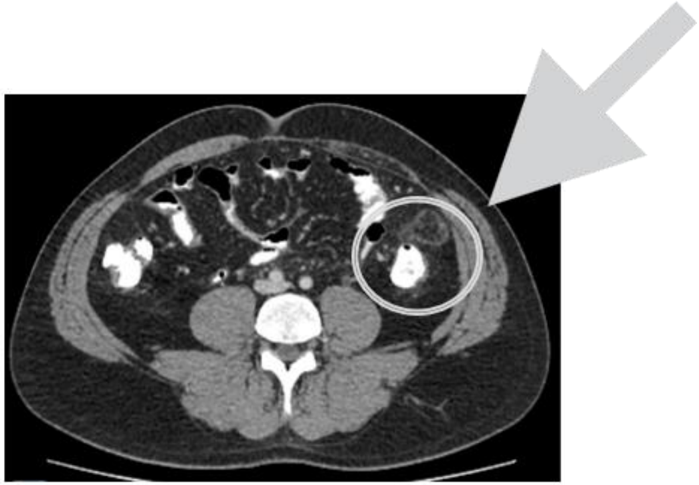

Homem, 47 anos, se apresenta ao Pronto Socorro com dor em fossa ilíaca esquerda há 1 dia sem febre ou demais sintomas. Nega episódios semelhantes ou cirurgias prévias. No exame físico, está em bom estado geral, normocárdico, afebril, abdome flácido, com dor localizada em fossa ilíaca esquerda, sem dor à descompressão brusca. Hemoglobina 14,8 g/dL (normal 12-16g/dL), Leucócitos 8750 s/ desvio (normal 6-10 mil), Proteína C Reativa 9 mg/L (normal até 5 mg/L). Realizada Tomografia, que observou a seguinte imagem.

Aponte o tratamento mais adequado: